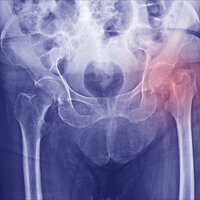

Skandinavia har den høyeste hyppigheten av hoftebrudd i verden, og hoftebrudd er et alvorlig folkehelseproblem (1–2).

Rundt 9800 pasienter rammes årlig i Norge (3), og ved Akershus universitetssykehus opereres om lag 600 av disse pasientene. Pasientgruppen består hovedsakelig av eldre som har falt fra egen høyde og kommer inn som øyeblikkelig hjelp. De har ofte redusert allmenntilstand, flere diagnoser og sammensatte fysiske, psykiske og sosiale problemstillinger (2–6).

Forverret funksjonsnivå og høy dødelighet postoperativt henger i stor grad sammen med skrøpelighet og komorbiditet, men kan i tillegg tilskrives komplikasjoner som oppstår underveis i sykdomsforløpet (5–7). Noen av de viktigste komplikasjonene under sykehusoppholdet er knyttet til selve operasjonen, slik som langt tidsspenn mellom bruddet og operasjonen, det vil si mer enn 48 timer, og komplikasjoner under selve operasjonen (5–6).